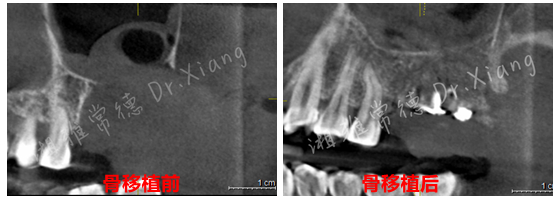

2024年末,該患者因外院不正規(guī)的拔牙造成左上頜大面積骨缺損。為尋求頜骨修復,在常德多家醫(yī)療機構就診,均告知難度大建議前往長沙?;颊卟幌氡疾?,經(jīng)朋友介紹后來到湘雅常德醫(yī)院就診??谇豢浦魅挝闂澖釉\了患者并為患者制定了詳細的治療計劃。伍棟主任指出:患者因拔牙造成頜骨大面積缺損,目前需要分二步處理。第一,先行頜骨缺損的骨移植;第二,待骨移植成功后,再行缺牙的種植修復。經(jīng)過周密的術前規(guī)劃和準備,口腔頜面外科團隊在全身麻醉下為患者成功施行了游離髂骨移植修復術+牙槽植骨成形術”。手術團隊巧妙地以患者自身的髂骨作為移植材料,采用數(shù)字化3D設計與打印技術,在術中精準截取髂骨并完成上頜骨缺損的定制化重建,成功恢復頜骨及牙槽嵴的生理性高度與寬度,實現(xiàn)解剖結構的精準復原,并應用了微型鈦板鈦釘內(nèi)固定系統(tǒng)來確保移植骨的穩(wěn)定愈合。

經(jīng)過9個月骨愈合后,患者復查錐形束CT,骨愈合十分滿意。9月中旬,向峰醫(yī)師種植團隊成功為患者實施了第二步的手術,取出內(nèi)固定裝置的同時為患者成功微創(chuàng)的植入2枚種植體,完成了患者左上頜區(qū)域的軟硬組織的自然恢復和改建。